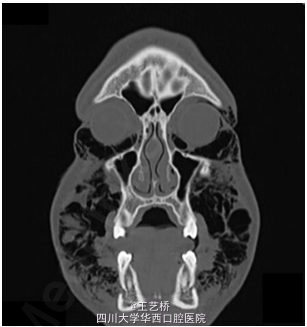

患者拔除双侧智齿后当天出现面部肿胀

检查发现患者整个面部肿胀,皮温正常,睁眼困难,轻度张口受限,轻度呼吸急促。触诊发现眶周、脸颊部、锁骨上窝有清脆捻发音。口内拔牙窝未愈合。

诊断:皮下气肿。患者住院进行预防性抗感染治疗,服用类固醇,同时为了避免软组织内气压过大,使用引流管控制气压